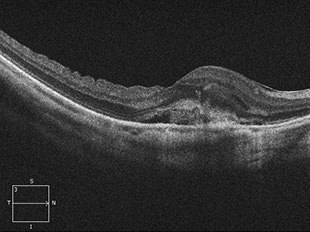

網膜静脈閉塞症

網膜静脈閉塞症は、網膜の静脈が詰まった状態で発症します。網膜の静脈が詰まると静脈の圧力が上がり、網膜の血管が広がったり、蛇行したり、出血したりします。また、網膜に血液中の水分がたまり黄斑付近に発症すると黄斑浮腫を起こします。

網膜の静脈が詰まってしまうため、網膜に出血や浮腫が起こります。そのため、ものが見えにくくなる、見えない部分があるなどの症状が出ます。特に黄斑部分に出血や浮腫ができると、視力が急に下がったり、かすんだり、黒く見えたり、歪んで見えたりします。

治療前 OCT

治療後 OCT